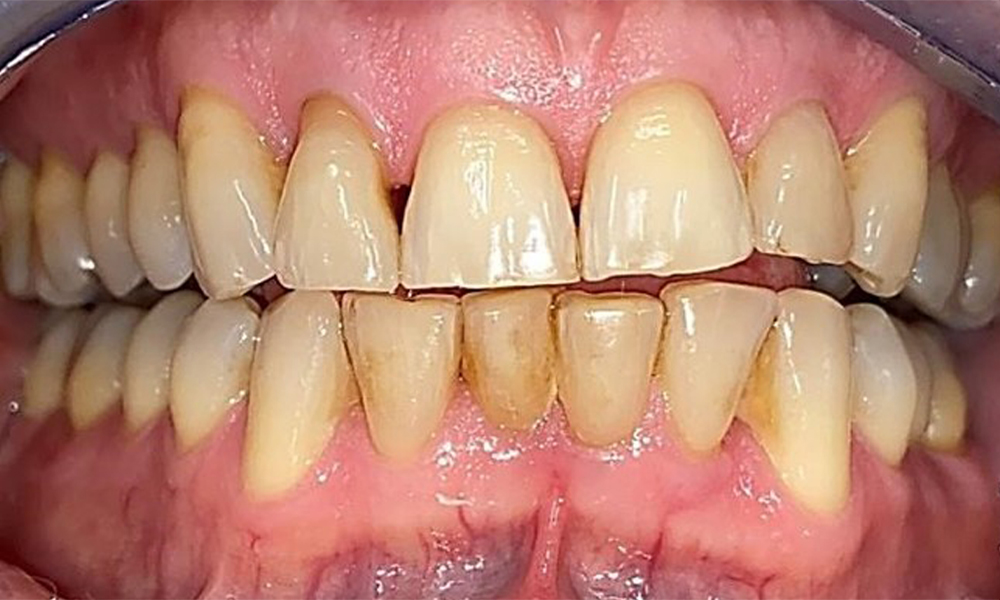

Frontal view with loss of the interdental papillae between 12 and 11.

Fig. 2 Frontal view with loss of the interdental papillae between 12 and 11. © Dr R. Krapf

The patient has stage II, grade B periodontitis (5). At 1 to 3 mm, the clinical probing depths were within the physiological range. Localized probing depths of 5 mm were observed on the mesiopalatal aspects on both 17 and 27. There are generalized recessions of 1–3 mm with partial loss of the interdental papillae (Fig. 2, Fig. 3, Fig. 4)